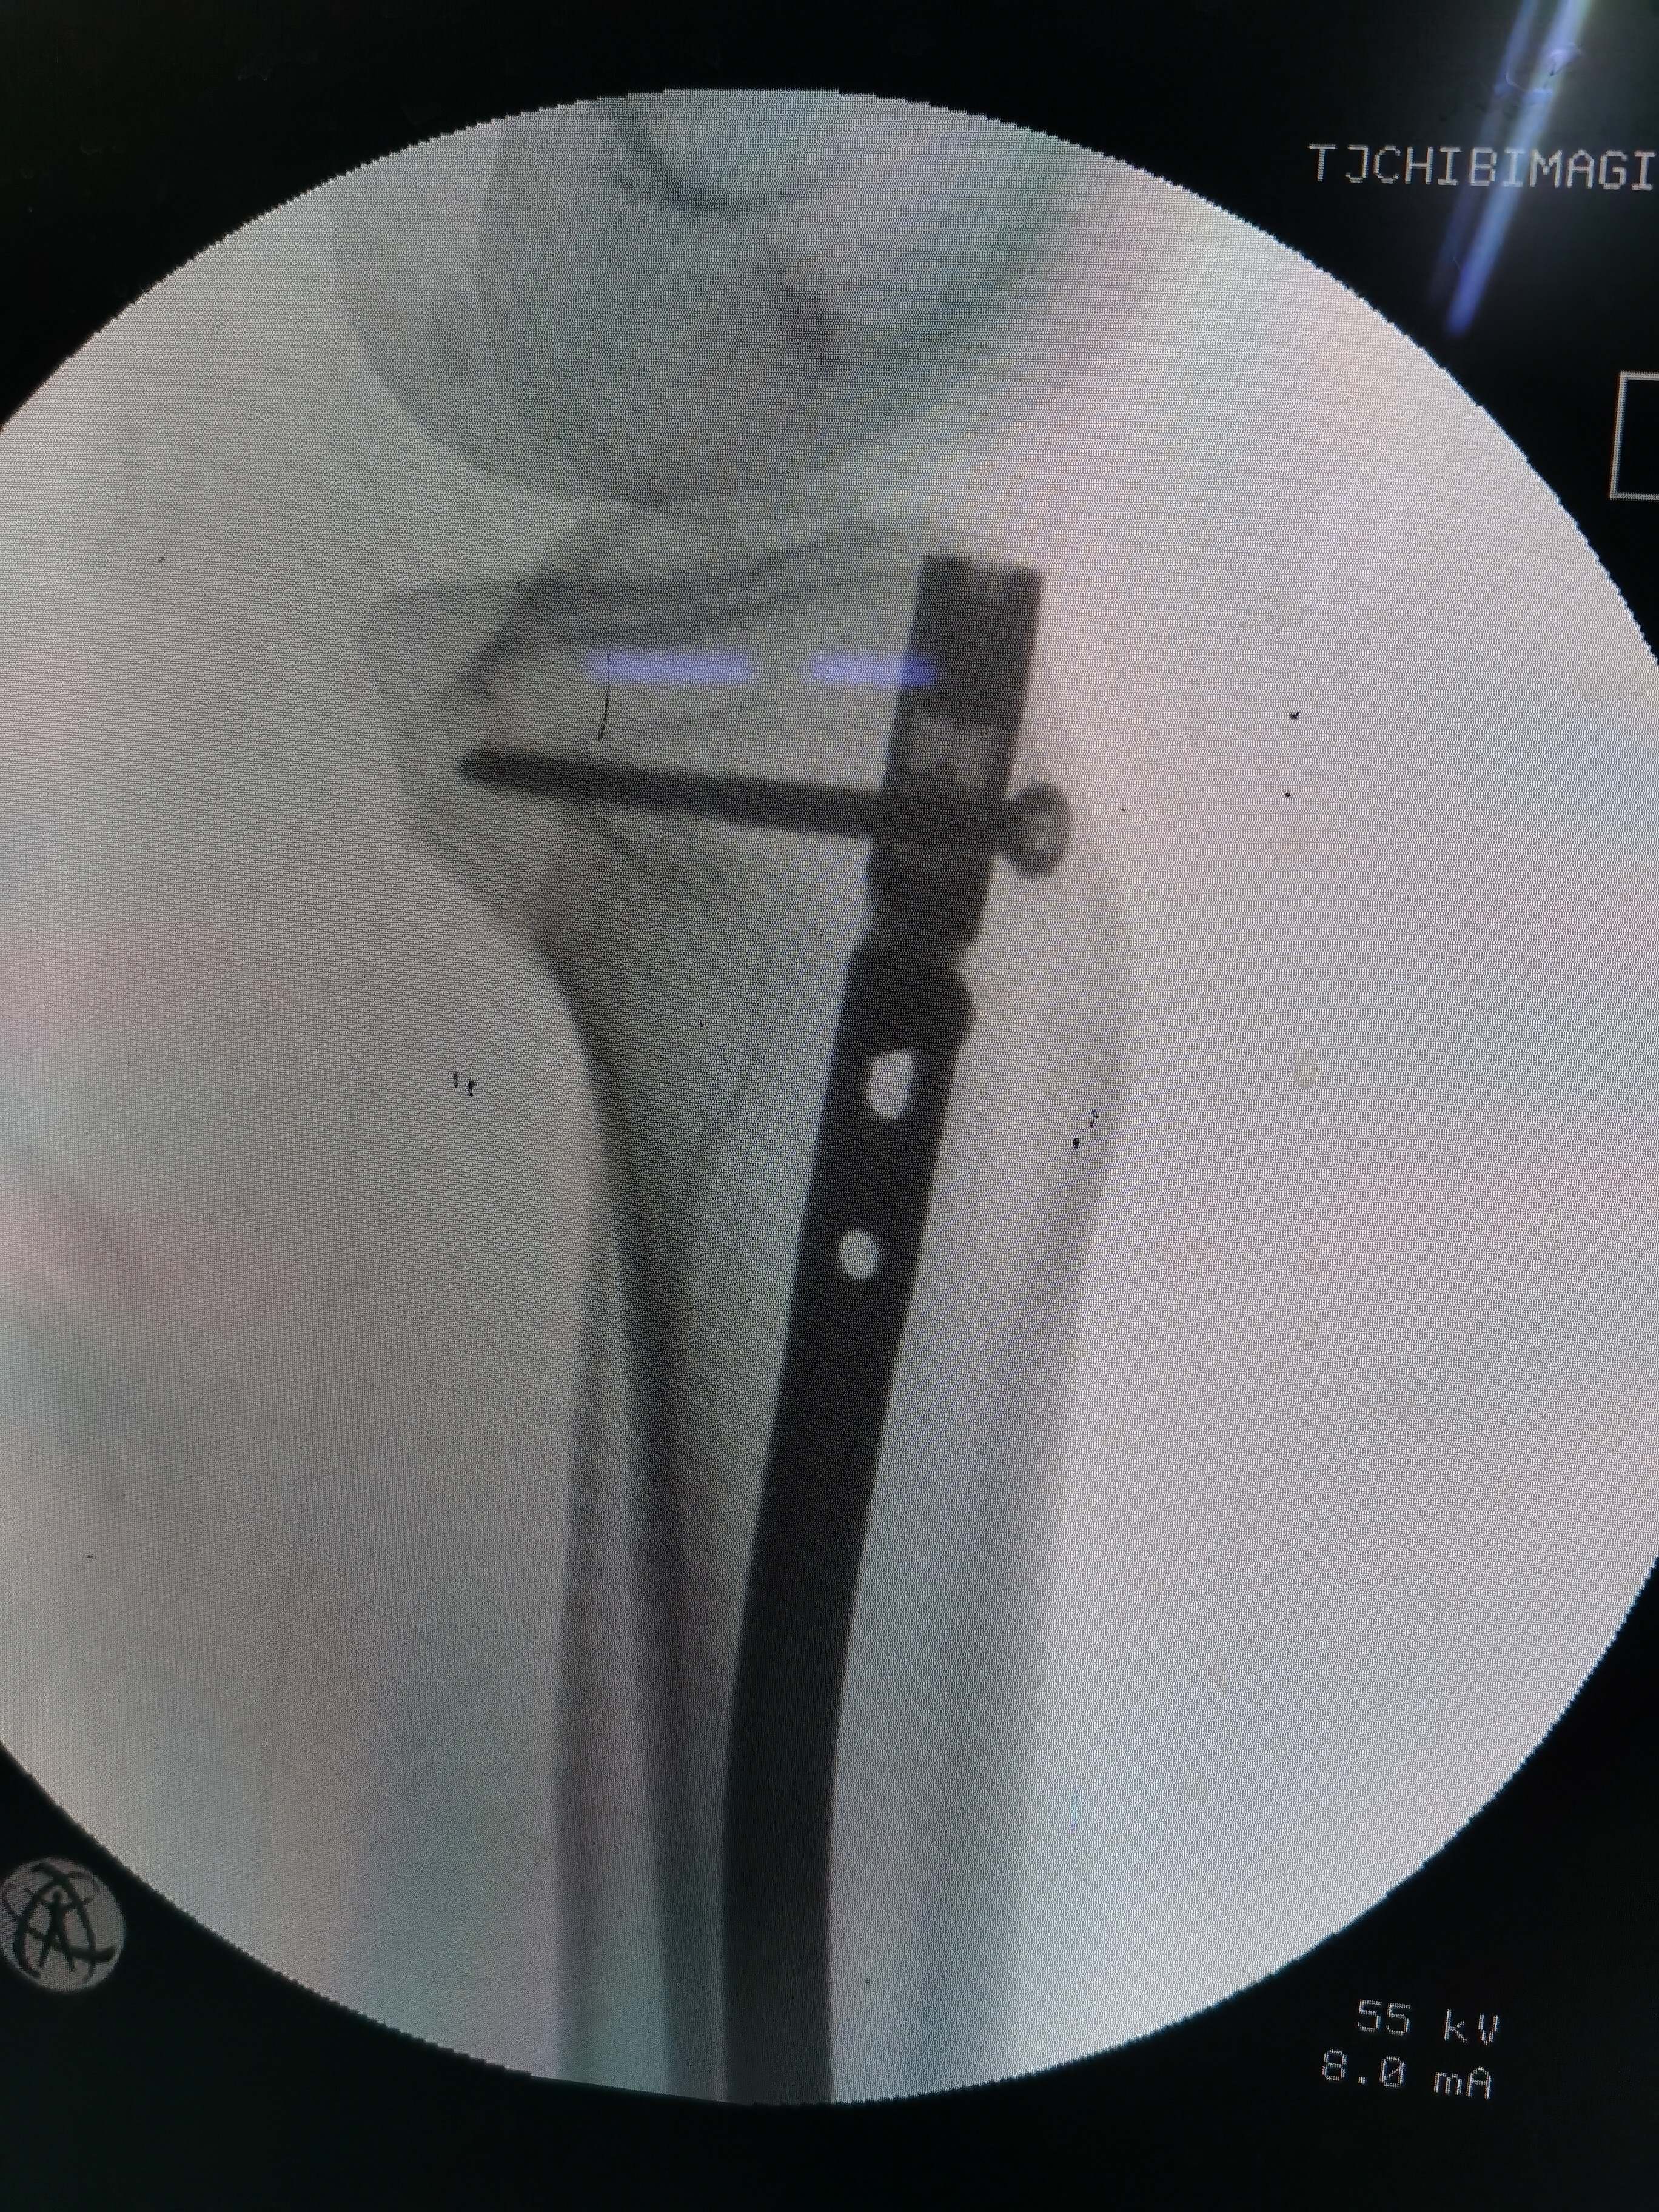

术中透视近端

患者男,53岁,因外伤致右胫骨中段粉碎性骨折。内踝前方有片状皮肤擦伤。入院后完善术前检查,给予石膏托固定,消肿处理。评估手术风险后,在腰硬联合麻醉下行右胫骨骨折闭合复位交锁髓内钉固定。术中屈曲膝关节,传统髌韧带入路,锥形开口后置入导针,金手指插入复位,扩髓,植入10mmx340mm髓内钉,远近端锁钉。手术顺利,因盲打远端锁钉,反复调整了几次,手术时间一个半小时,未使用止血带,出血约100m1。